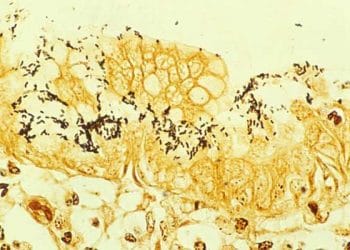

Warthin-Starry Gümüş Boyası, Bartonella ve spiroketlerin boyanmasında kullanılan, yaymalarda ve doku kesitlerine uygulanan boyama yöntemine denir. Warthin-Starry Silver Stain